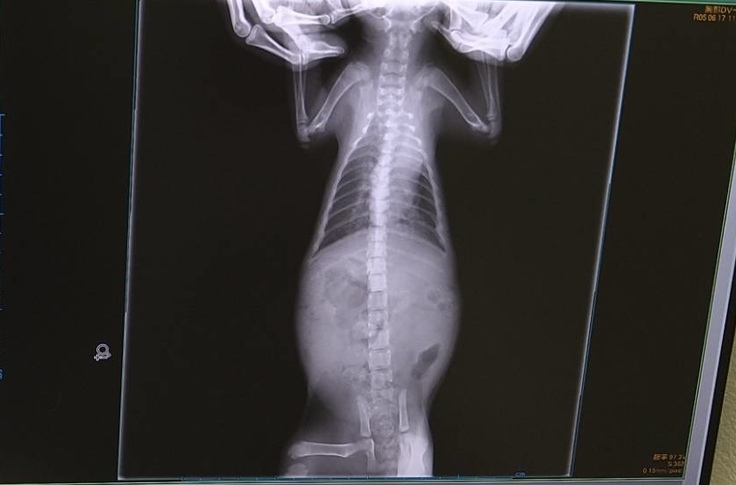

6月17日 通院

今日は動物病院通院日でした。

肺炎と漏斗胸の経過観察のため、レントゲンを撮ってもらいました。

ヤマトは「悪いながらに良くなっている」と言われました。ナイトは「肺炎・漏斗胸ともに少しずつ良くなってきている」と言われました。ヤマトはまだまだ心配ですが、2匹ともこれからも内服を頑張り、週1回通院していこうと思います。